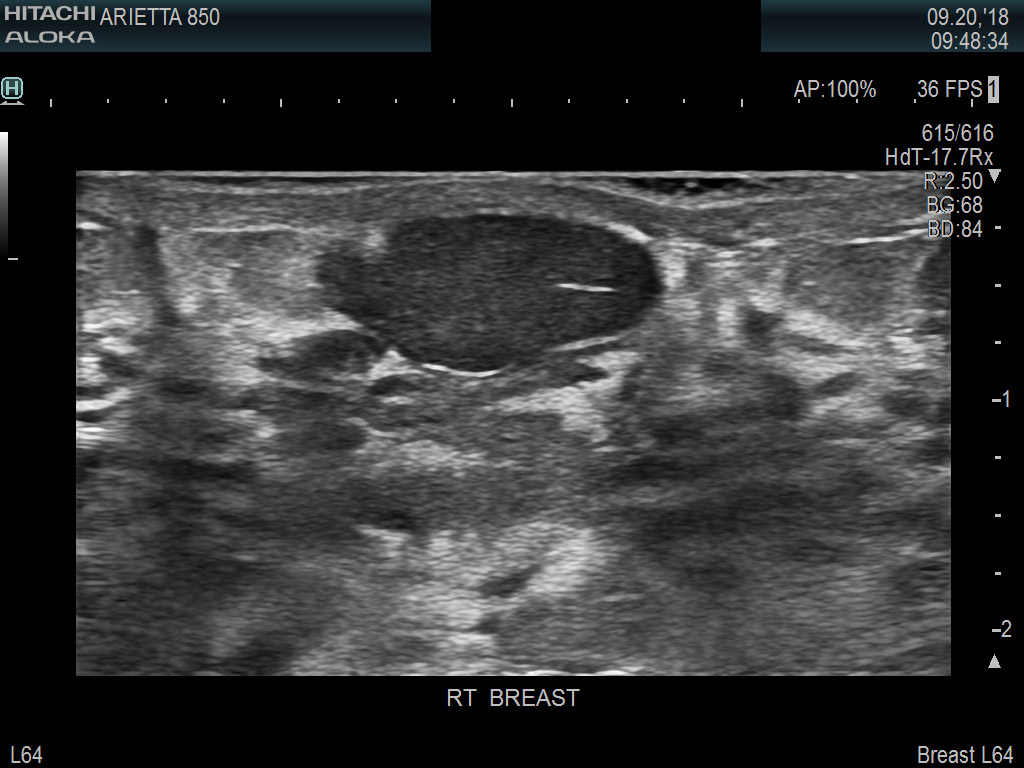

Superior guidance for all applications

Fujifilm Healthcare's dedication to Surgeons provides outstanding ultrasound technology, professional support and the specialized tools necessary to best perform comprehensive real-time ultrasound imaging in Breast Surgery, General Surgery, Laparoscopic Surgery, Neurosurgery, Robotic Surgery and Surgical Oncology.

Recognized for our outstanding image quality, outstanding system reliability and intuitive use of cutting edge technology, Fujifilm Healthcare remains the standard in the field of Surgery.

Recognized for our outstanding image quality, outstanding system reliability and intuitive use of cutting edge technology, Fujifilm Healthcare remains the standard in the field of Surgery.